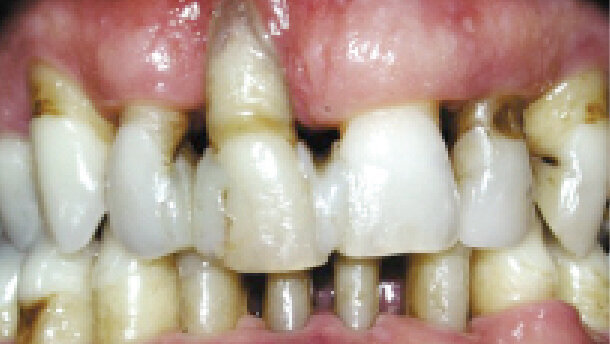

Pacientem byl celkově zdravý 47letý muž. Stěžoval si na pohyblivost zubu (konkrétně zubu 11), která byla důvodem jeho návštěvy zubního lékaře. Jeho zubní lékař tento zub provizorně zdlahoval (obr. 1). Při vyšetření byl ve všech oblastech zjištěn velmi výrazný úbytek kosti (obr. 2), hluboké choboty a krvácení při sondáži. Kromě příležitostného odstraňování zubního kamene a depurace nebylo zjištěno žádné jiné ošetření parodontu a hygiena dutiny ústní byla prováděna řádně.

Navzdory tomu, jak se na rentgenovém snímku zdál být stupeň úbytku kosti výrazný, byla po počátečním ošetření zjištěna mobilita I. stupně a všechny zuby byly funkčně stabilní. Celkově se postupně zlepšilo i krvácení a hloubka chobotů, ale na mnoha místech v dolní čelisti zůstávaly hluboké choboty, které dobře reagovaly na parodontální chirurgii (obr. 3). Jakmile bylo dosaženo celkové stability parodontu (nepřítomnost parodontálních chobotů > 4 mm, zanedbatelná přítomnost krvácení při sondáži, dobrá orální hygiena a fyziologická pohyblivost), byla navržena přísná udržovací léčba, která by měla zabránit opakovaným projevům onemocnění (obr. 4 a 5).